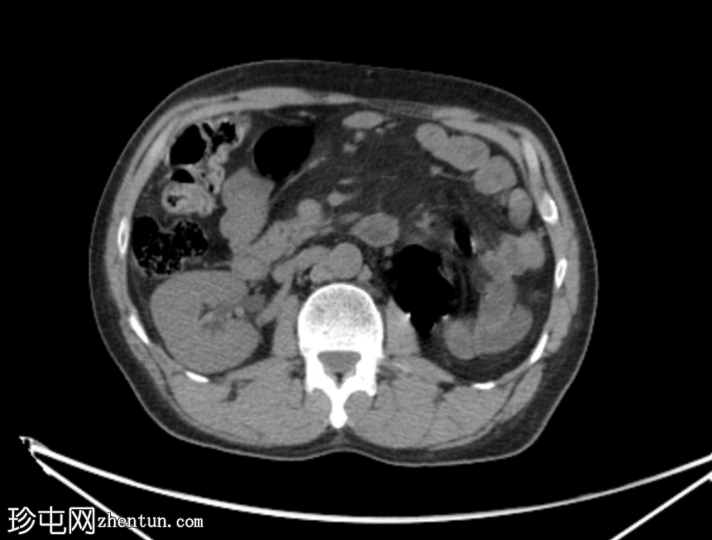

CT

轴位

平扫

左肾发育不全。

左侧精囊发育不全。

肠系膜脂肪炎伴肠系膜脂肪间隙模糊及肠系膜淋巴结肿大。

肠系膜可见一小块钙化灶,提示钙化性淋巴结,系既往肉芽肿性感染的后遗症。